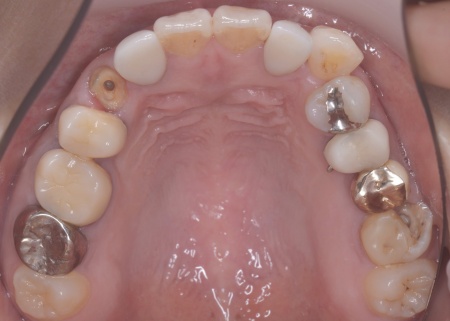

40代女性 矯正治療で噛み合わせを整えたあとセラミックの被せ物・詰め物で修復した症例

拝見したところ、左下と右上の歯はともに大きな虫歯があり、歯だけでなく被せ物を支える土台の部分にも影響が及んでいました。

さらに、ほかの歯に入っている詰め物や被せ物の周囲にも、過去に治療した部分に再び虫歯ができる二次カリエスが複数見つかりました。

まずは矯正治療を優先し、噛み合わせが整ってから虫歯の再発リスクの低いセラミックの被せ物・詰め物などで歯の形態と機能を回復する方針を提案し、同意いただきました。

矯正治療終了後、改めてお口の中を確認したうえで、歯の状態に合わせ虫歯の除去や土台の修復を丁寧に行い、精密な型取りを実施しています。

なお、左上の奥歯には人工歯根を埋め込んで失った歯を補うインプラントが装着されていたものの、人工歯根の位置や骨との結合状態に問題はありませんでした。

そのため、人工歯根部分はそのまま活用し上部に装着する人工歯のみを新しく作製しています。

最後に噛み合わせ全体のバランスを確認しながら新しく作製した被せ物や詰め物を装着し、見た目に問題がないか、噛み合わせが安定しているかを確認し、治療を終了しました。